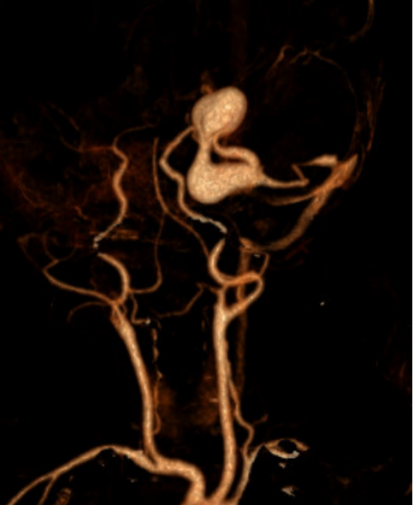

该院神经外科主任医师王超接诊后,第一时间为木木进行详细查体,凭借丰富的临床经验,高度怀疑患儿颅内出血是由血管畸形破裂所致,当即决定联系影像科完善头颅CT及血管成像检查,以进一步明确病因。

“CT检查证实,木木的颅内出血确实源于脑动静脉畸形破裂。”王超表示,“更棘手的是,我们在患儿供血动脉处发现了两个巨大的瘤样鼓包,患儿情况不容乐观。”